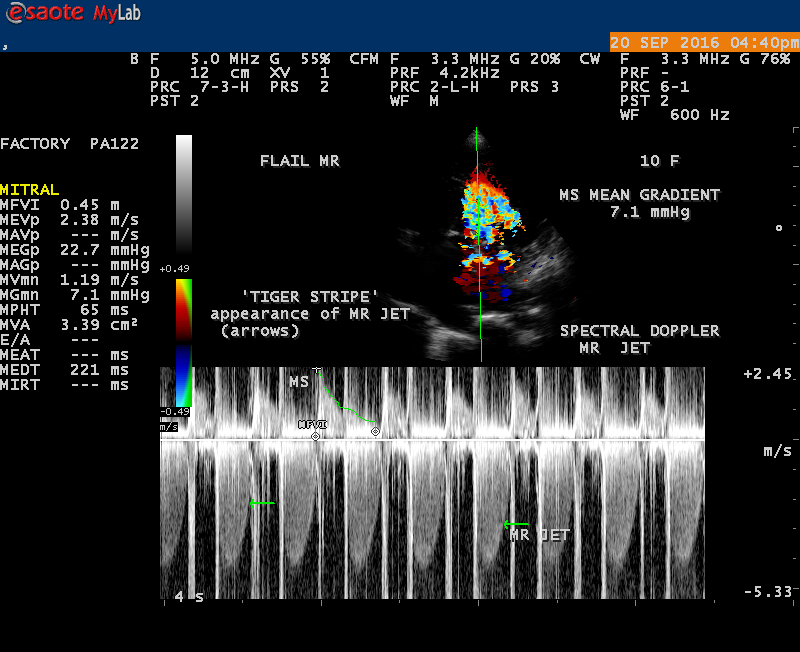

The most common and direct evidence of infective endocarditis is the vegetation and it begins as a microscopic focus of infection and gradually grows into a conspicuous mass. It is typically an irregularly shaped, highly mobile, echogenic mass attached to the free edge of a valve leaflet ( most commonly at the coaptation line) and tends to develop on the ‘upstream’ side of the valve leaflets ( ie, the ventricular side of aortic valve and the atrial side of mitral and tricuspid valves. They may be seesile or pedunculated, but usually has an oscillating or fluttering motion, a typical feature of most vegetations. Vegetation move with the leaflet in a more chaotic (‘oscillating’) manner and it may prolapse through the valve into the LV (left ventricle) as it opens as shown in Figures 3, 4 and 16 and into LA (left atrium) as it closing (Figure 5 and 6) . The mass of vegetation is typically homogeneous with echogenicity similar to that of the myocardium. The infectious process often alter the valvular structure and function. Extensive involvement of the leaflet may result in chordal rupture, leading to severe regurgitation as shown in Figure 21 . Direct and typical signs of RMCT (ruptured mitral chordate tendineae) were chain-flail or whiplash-like changes and had an incidence of 86.7%, causing severe regurgitation and mitral chordal rupture is the leading cause of flail mitral leaflet[30]. A large vegetation may obstruct the valve orifice as shown in Figure 1 and 2 , sometimes termed as “obstructive-type bacterial endocarditis” and producing a functional valve stenosis ( Ping-Pong mitral stenosis [31]) similar to left atrial myxoma as shown in Figure 29.

The size and shape of vegetation vary due to curling of vegetation. The size of vegetation in this child is 35.6 x 9.3 mm as in Figure 17 , 20 x 23.7 mm as in Figure 1 , 32.9 x 13.9 mm as in Figure 2 .

The shape of vegetation varies in this child as ‘popcorn’ like (Figures 1,3 and 4 ), rod-shaped (Figure ), basket shaped (Figure 7 )[33-Figure 13.3], ‘baby in hand’ appearance (Figure 18), ‘cucumber shaped (Figure 2 ) and a ‘bunch of plantain’appearance (Figure 33 ), ring shaped (Figure 19 }, bileaflet structure (Figure 9 )with bileaflet MR jet as shown in Figure 10 . and kissing forms (Figure 13 - parasternal long axis view, Figure 14 - apical four chamber view and Figure 15 - short axis view)

‘Flail’ Mitral Regurgitation (MR)

The anatomic disruption of a portion of the mitral valve apparatus dueto the underlying rheumatic valvulitis with predisposing infective endocarditis which form a vegetation , resulting an eccentric regurgitation jet with orientation opposite in direction of the leaflet having the anatomic defect such as ‘flail’. In the presence of ‘flail leaflet’, the mitral regurgitant spectral signal may have an atypical appearance and the flail portion oscillate in the spectral signal of regurgitant flow stream to produce a ‘tiger stripe’ appearance as shown in Figure 27. associated with ‘whistling’ sound on auscultation[33-Figure 11.85]. The mitral regurgitation (flail MR) jet is chaotic as shown in Figure 26, highly eccentric (Figure 22) and disorganized with one component behind the anterior mitral leaflet and the second component directed towards posterior immediately as in Figure 21 [33- Figure 11.79].